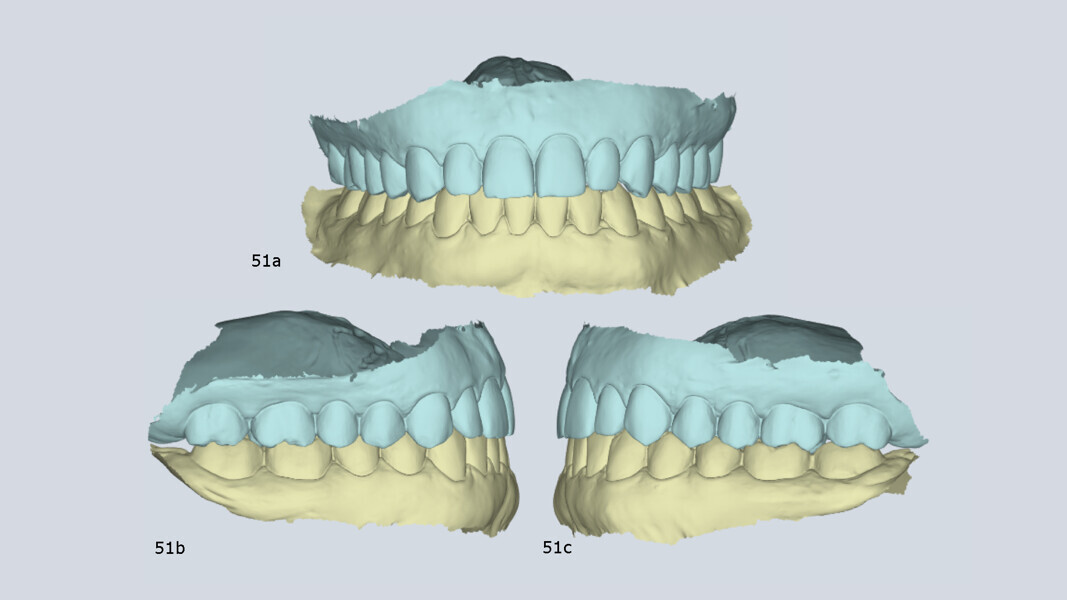

Finally, the treatment concluded with orthopaedic stability (maximum intercuspation coincided with centric occlusion), as well as with improved condylar position and morphology. The patient was also completely free of TMD symptoms (Fig. 51).